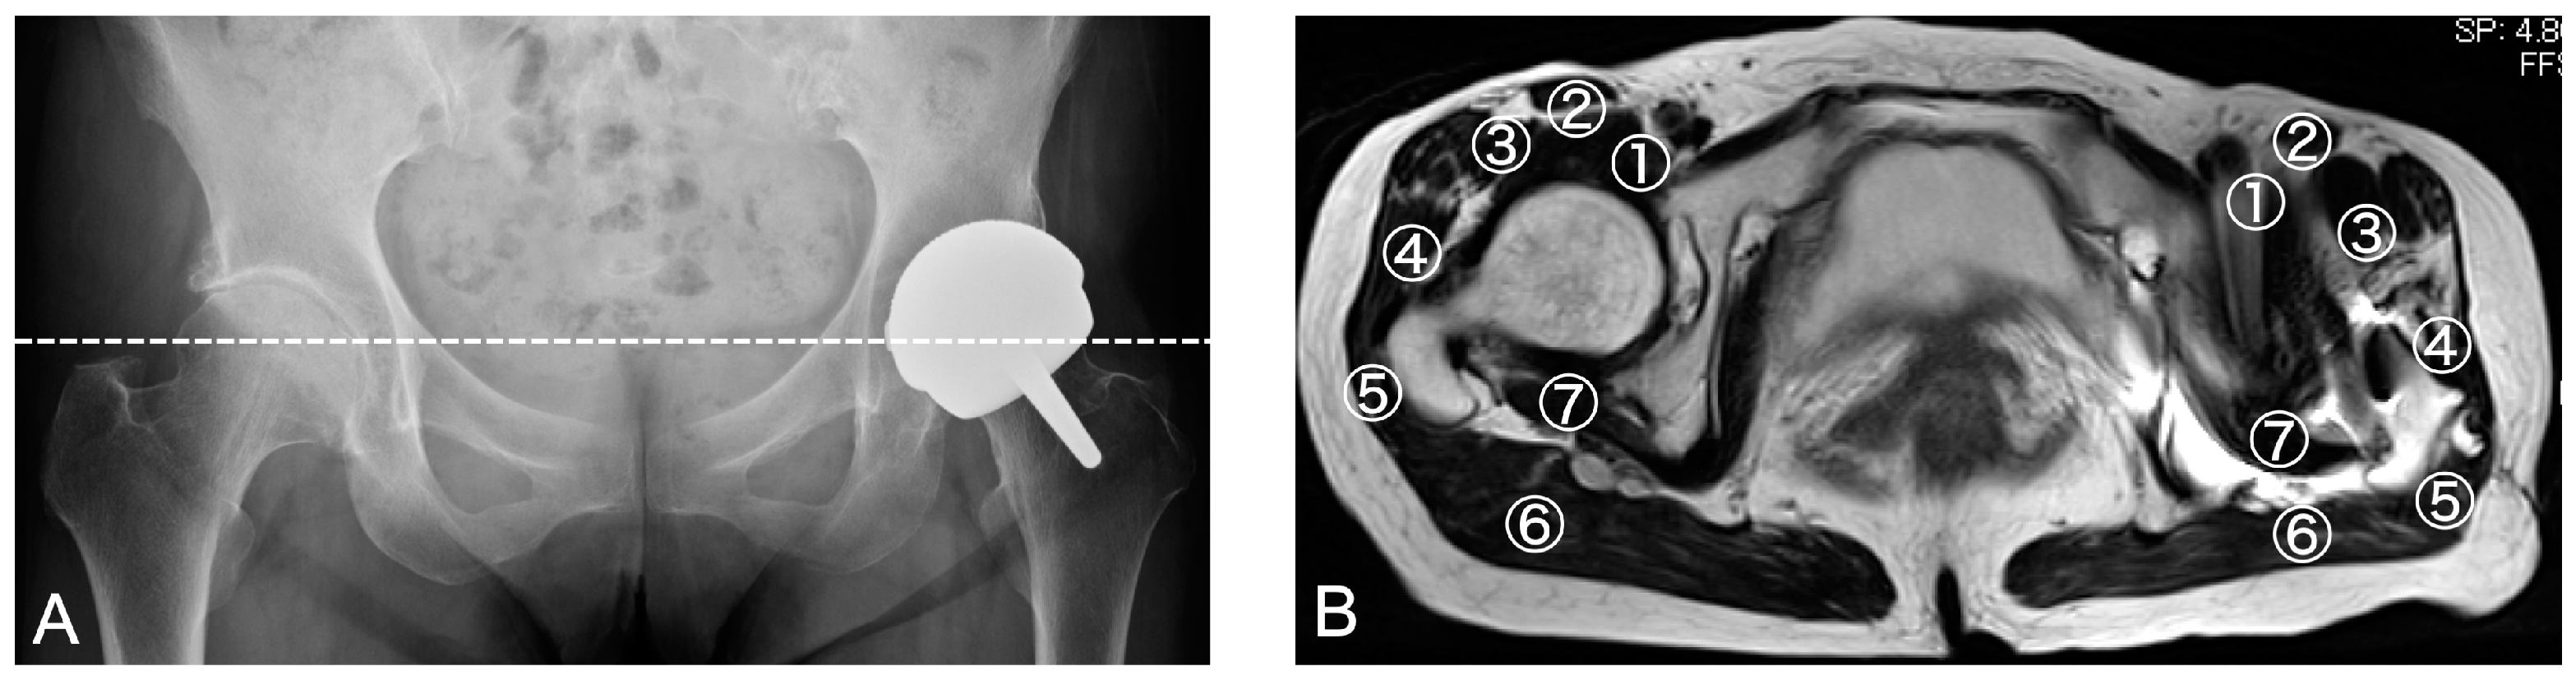

2.2. Ultrasonography

2.3. MRI